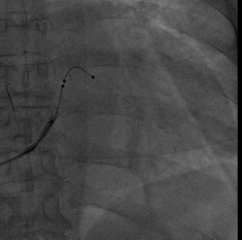

尝试抓捕器在右房抓捕runthough导丝成功,并进行牵拉

非常幸运,通过抓捕器的牵引力,电极顺利通过狭窄处,确定电极固定牢靠,抓捕器释放导丝并撤出,初步测试左室阈值满意,没有PNS。

依次植入右室除颤导线(6935M-DF4)和右房导线(4574),均测试满意,分别固定。

关键一步,鞘中鞘和递送鞘管的切除,均比较顺利,电极无移位。

AP

LAO45

RAO30